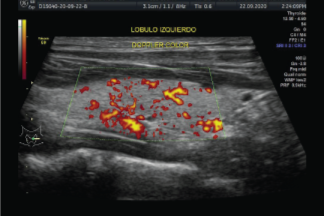

Una biopsia con aguja fina de un nódulo tiroideo es un procedimiento sencillo y seguro. Generalmente la biopsia se hace guiada por ultrasonido para asegurar la colocación precisa de la aguja en el nódulo tiroideo. El procedimiento es menos invasivo que la biopsia quirúrgica, deja poco o nada de cicatriz, y no involucra la exposición a la radiación ionizante.